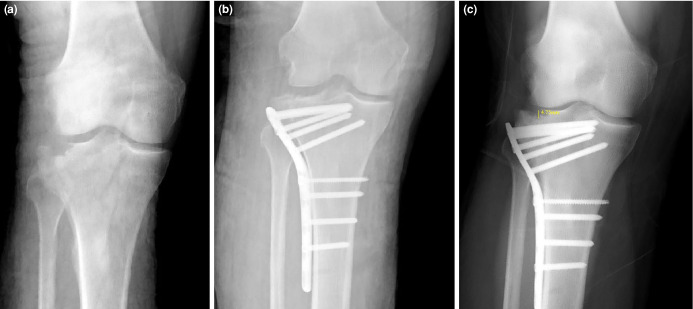

Objectives: This study aims to provide insight into the advantages and disadvantages of autograft and synthetic graft use in the surgical treatment of tibial plateau fractures with joint depression by comparing the clinical and radiological outcomes of both graft types.

Patients and methods: Between February 2019 and September 2022, a total of 51 patients (23 males, 28 females; mean age: 45.3±13.5 years; range, 20 to 69 years) who underwent surgical treatment for Schatzker type 2 and type 3 tibial plateau fractures in our clinic were retrospectively analyzed. The patients were divided into two groups; 30 patients received autografts and 21 received tricalcium phosphate synthetic grafts. Demographic data, graft type, fracture classification, preoperative joint depression, body mass index (BMI), and smoking status were recorded. Postoperative evaluations included Lysholm and Visual Analog Scale (VAS) scores at two years.

Results: Similar clinical and radiological outcomes were observed in both graft groups in the short term (p>0.05). Smoking had a negative effect on graft stability, with a significantly higher postoperative depression rate in smokers (p=0.026). Patients with a BMI above 30 kg/m2 also showed higher rates of postoperative depression (p=0.004). Clinical outcomes were worse in patients with joint depression compared to those without depression (p=0.003).

Conclusion: Autografts and synthetic grafts show similar efficacy in the mid-term treatment of tibial plateau fractures. High BMI and smoking may be associated with potential joint depression and worse clinical outcomes in the postoperative period.